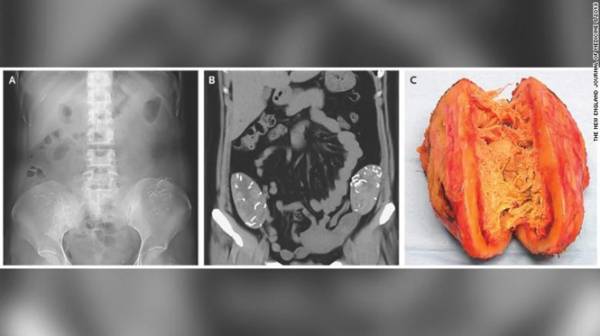

Ảnh chụp X-quang (trái), và chụp cắt lớp CT (giữa) đều cho thấy có hai băng gạc y tế nằm trong ổ bụng

Đó là kết quả sau khi chụp X-quang và chụp cắt lớp CT cho thấy có hai băng gạc y tế nằm trong ổ bụng người này.

Đài CNN dẫn lời bác sĩ Takeshi Kondo thuộc Bệnh viện Đại học Chiba (Nhật Bản) cho hay các băng gạc có thể bị bỏ quên sau một ca sinh mổ.

Người phụ nữ trên từng hai lần sinh mổ tại cùng một bệnh viện phụ sản, một lần cách đây 6 năm và một lần 9 năm về trước. Tuy nhiên, không rõ 2 băng gạc y tế trên bị bỏ quên trong thời điểm nào.

Sau ca phẫu thuật lấy dị vật, nạn nhân không còn bị đầy hơi và được xuất viện sau 5 ngày điều trị.